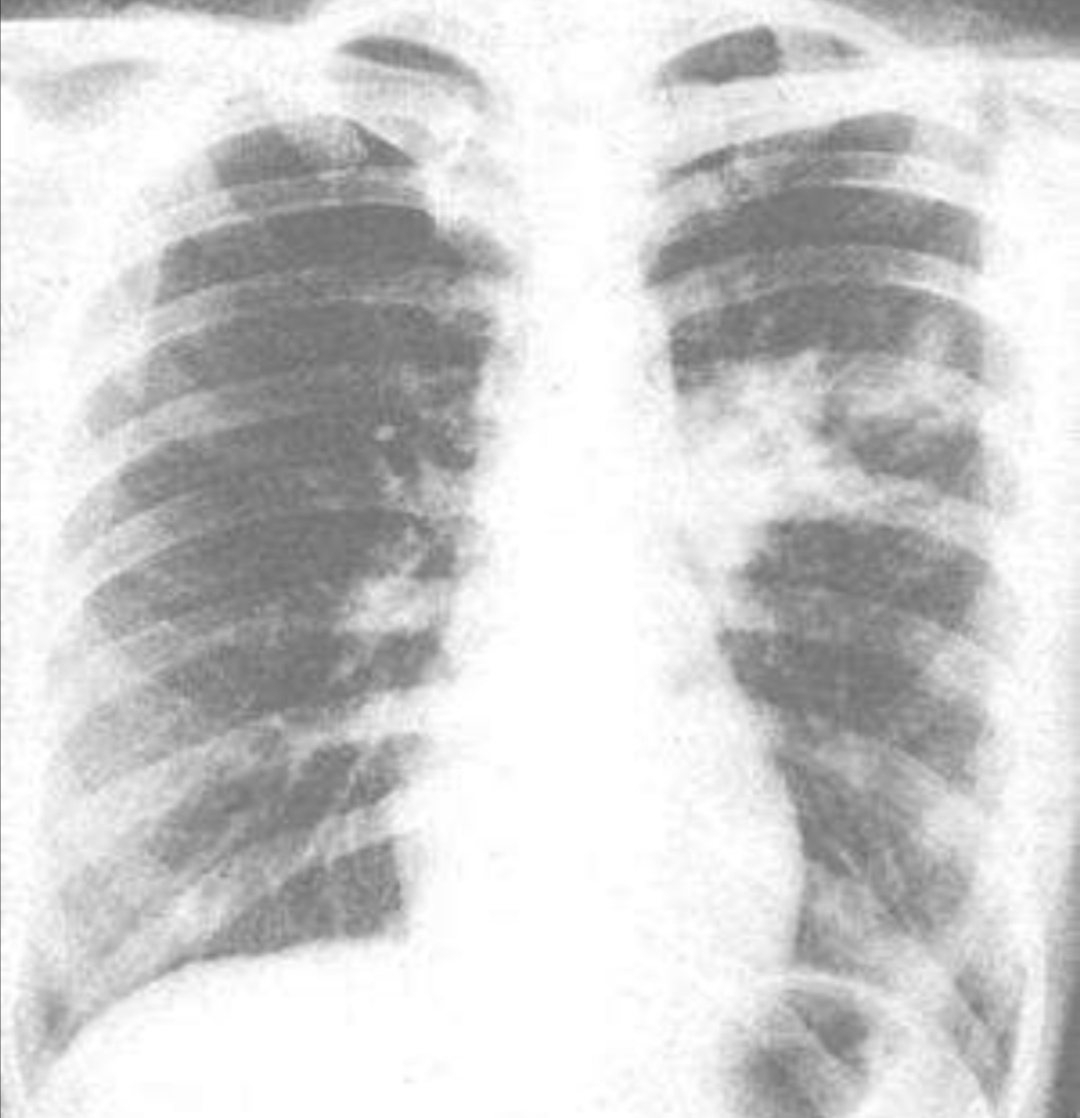

⑤肺部体征少,可有呼吸音减低,病程后期可出现湿性啰音。

⑥肺部体征与症状以及影像学表现不一致是肺炎支原体肺炎的特征。